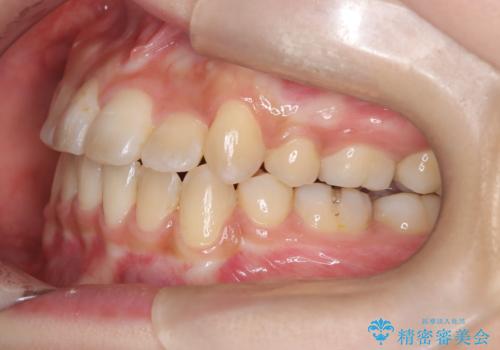

- 患者様は、歯並びのガタガタ(重度の叢生)を改善したいとのことで来院されました。診察すると、歯列のスペース不足が著しく、前歯が重なり合い、噛み合わせにも影響が出ている状態でした。歯をきれいに並べるためには抜歯によるスペース確保が不可欠と判断し、上下の小臼歯4本を抜歯したうえで、目立ちにくい審美ワイヤー矯正(白いワイヤーと透明ブラケット)を用いた治療計画を立てました。

抜歯によって歯を動かすためのスペースを確保。その後、審美ワイヤー矯正を用いて歯を1本ずつ適切な位置に誘導しながら、噛み合わせのバランスも整えていきました。時間はかかりましたが、ガタガタの歯並びがきれいに整い、機能的にも審美的にも満足のいく仕上がりとなりました。患者様からは「歯並びが劇的に改善し、見た目だけでなく噛みやすさも向上した」と喜びの声をいただきました。